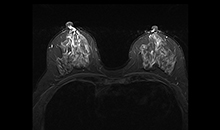

一体化线圈

无需更换线圈,即可进行多部位联合成像,缩短检查时间。